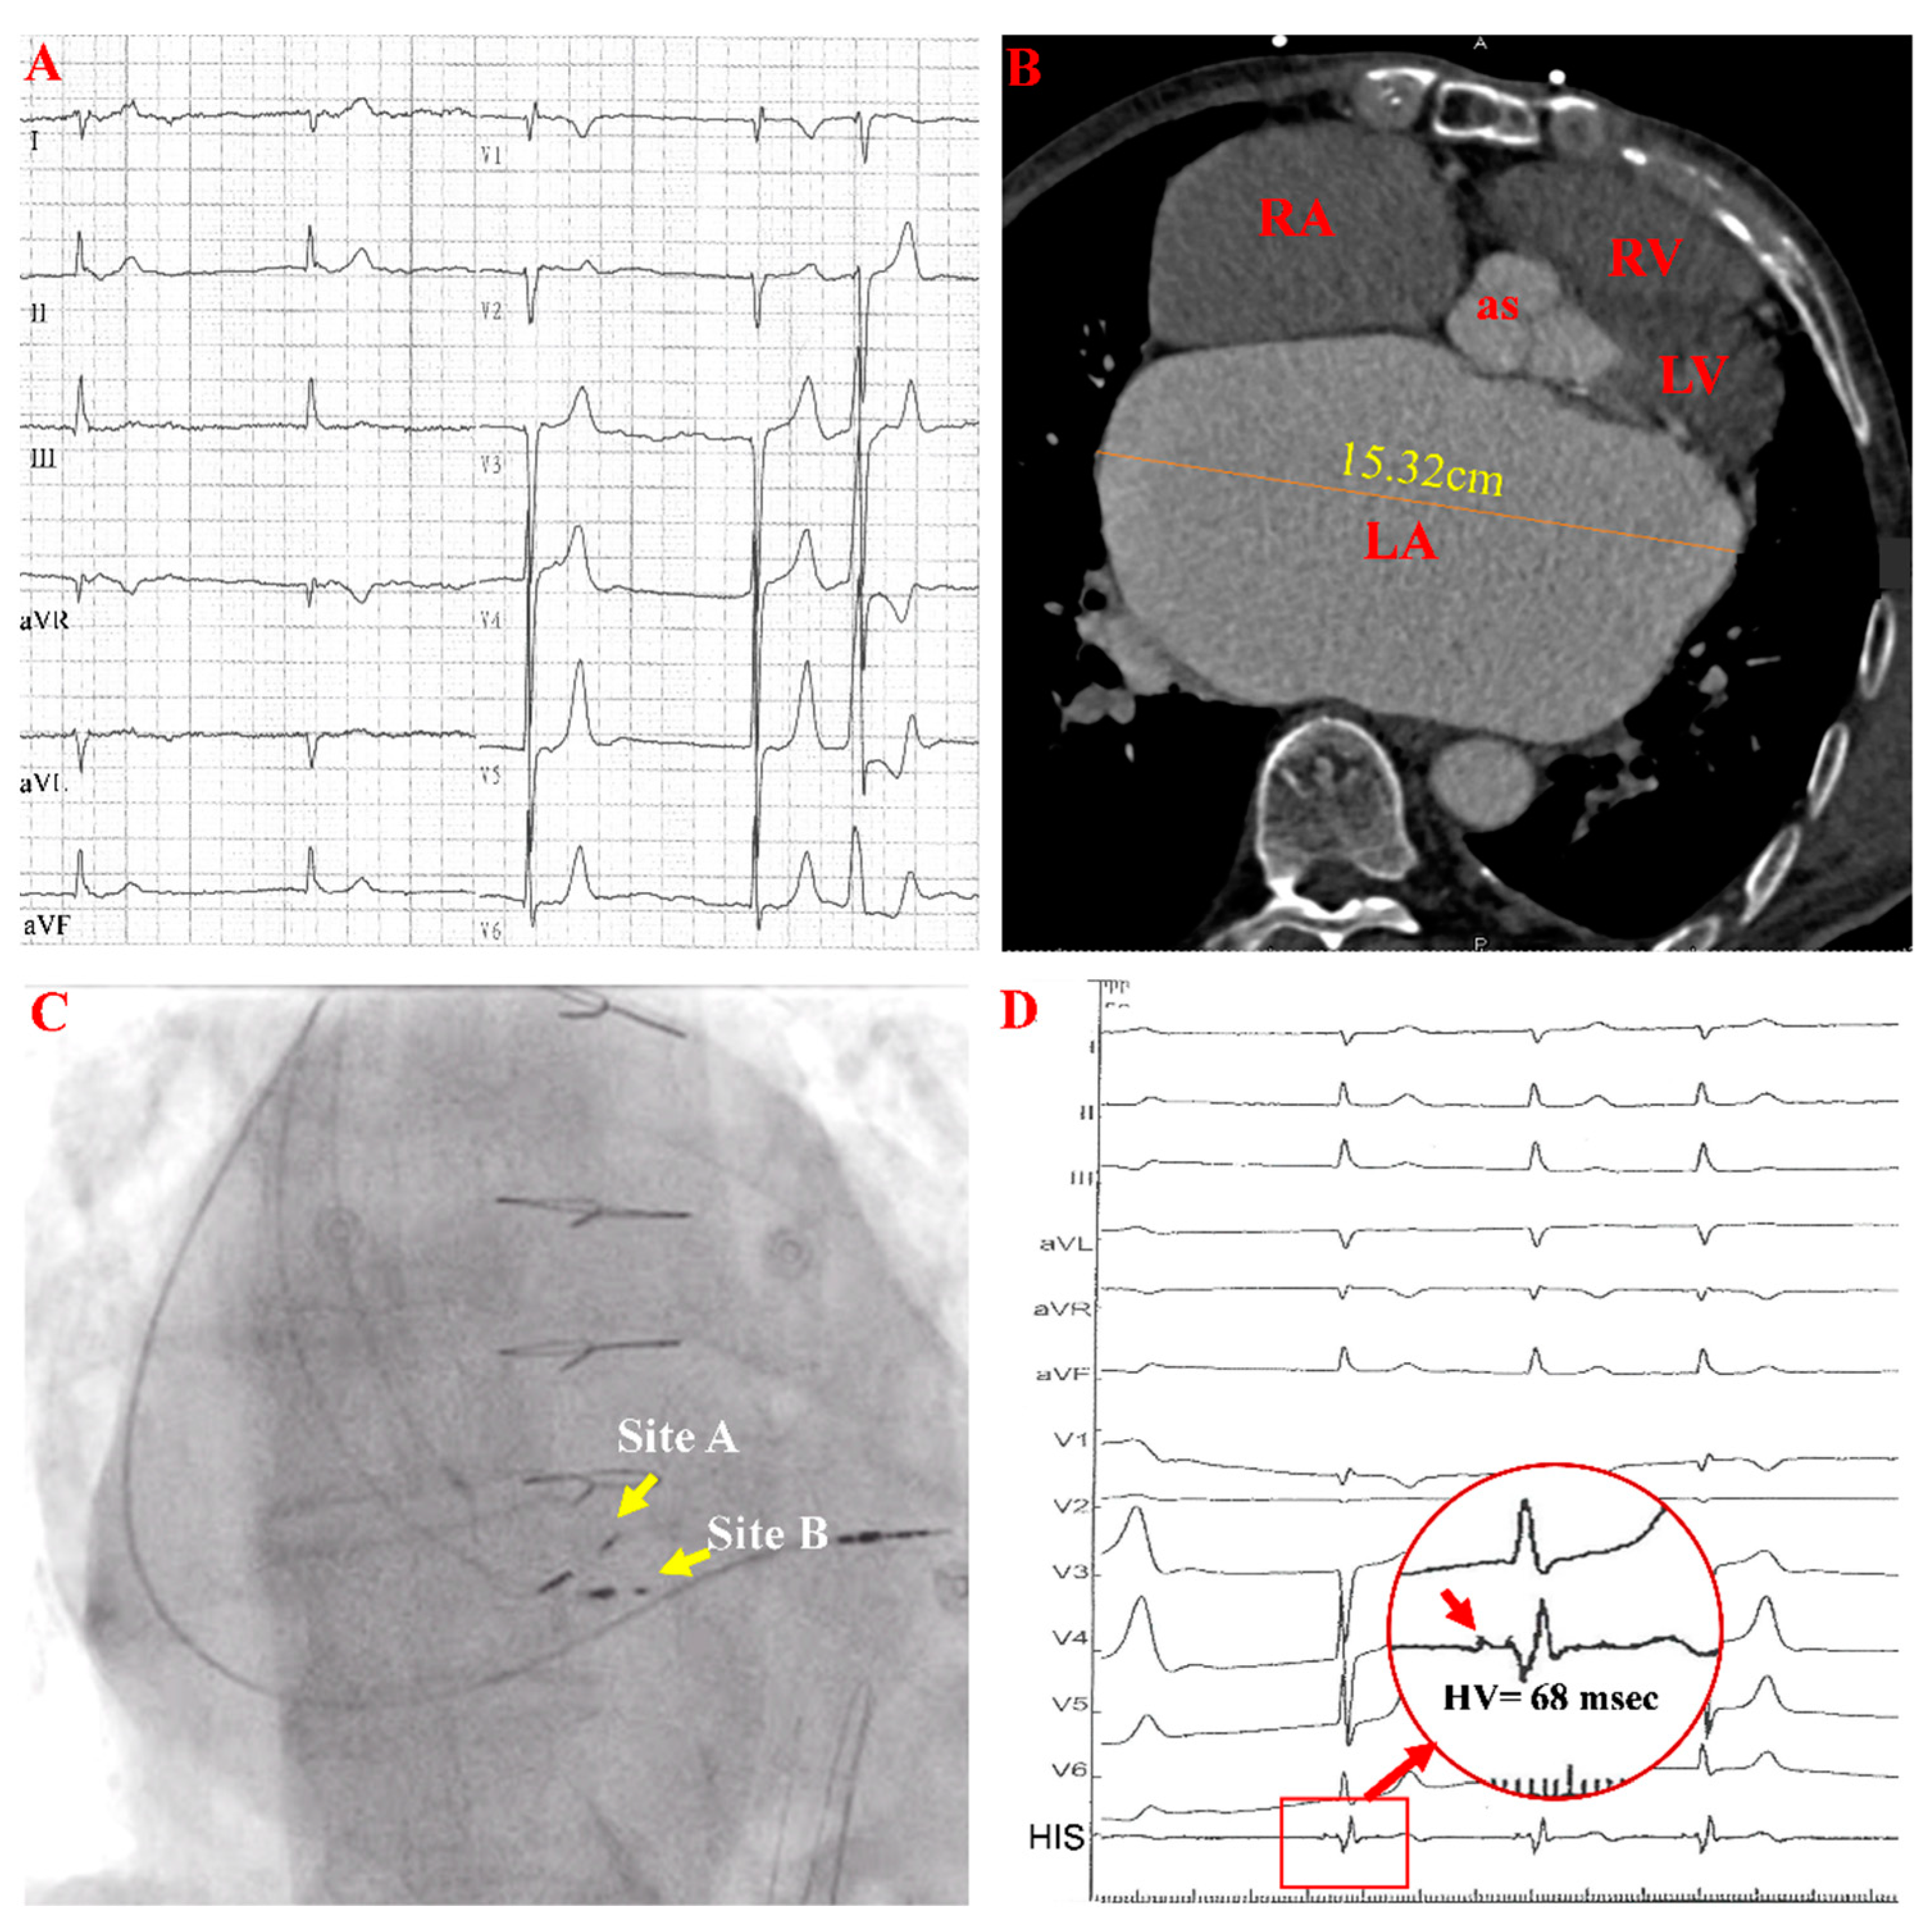

A Case Report of a Wenckebach Phenomenon Occurring during a His-Bundle Pacing Procedure: Is It Atrioventricular Node Pacing?

2. Case Report